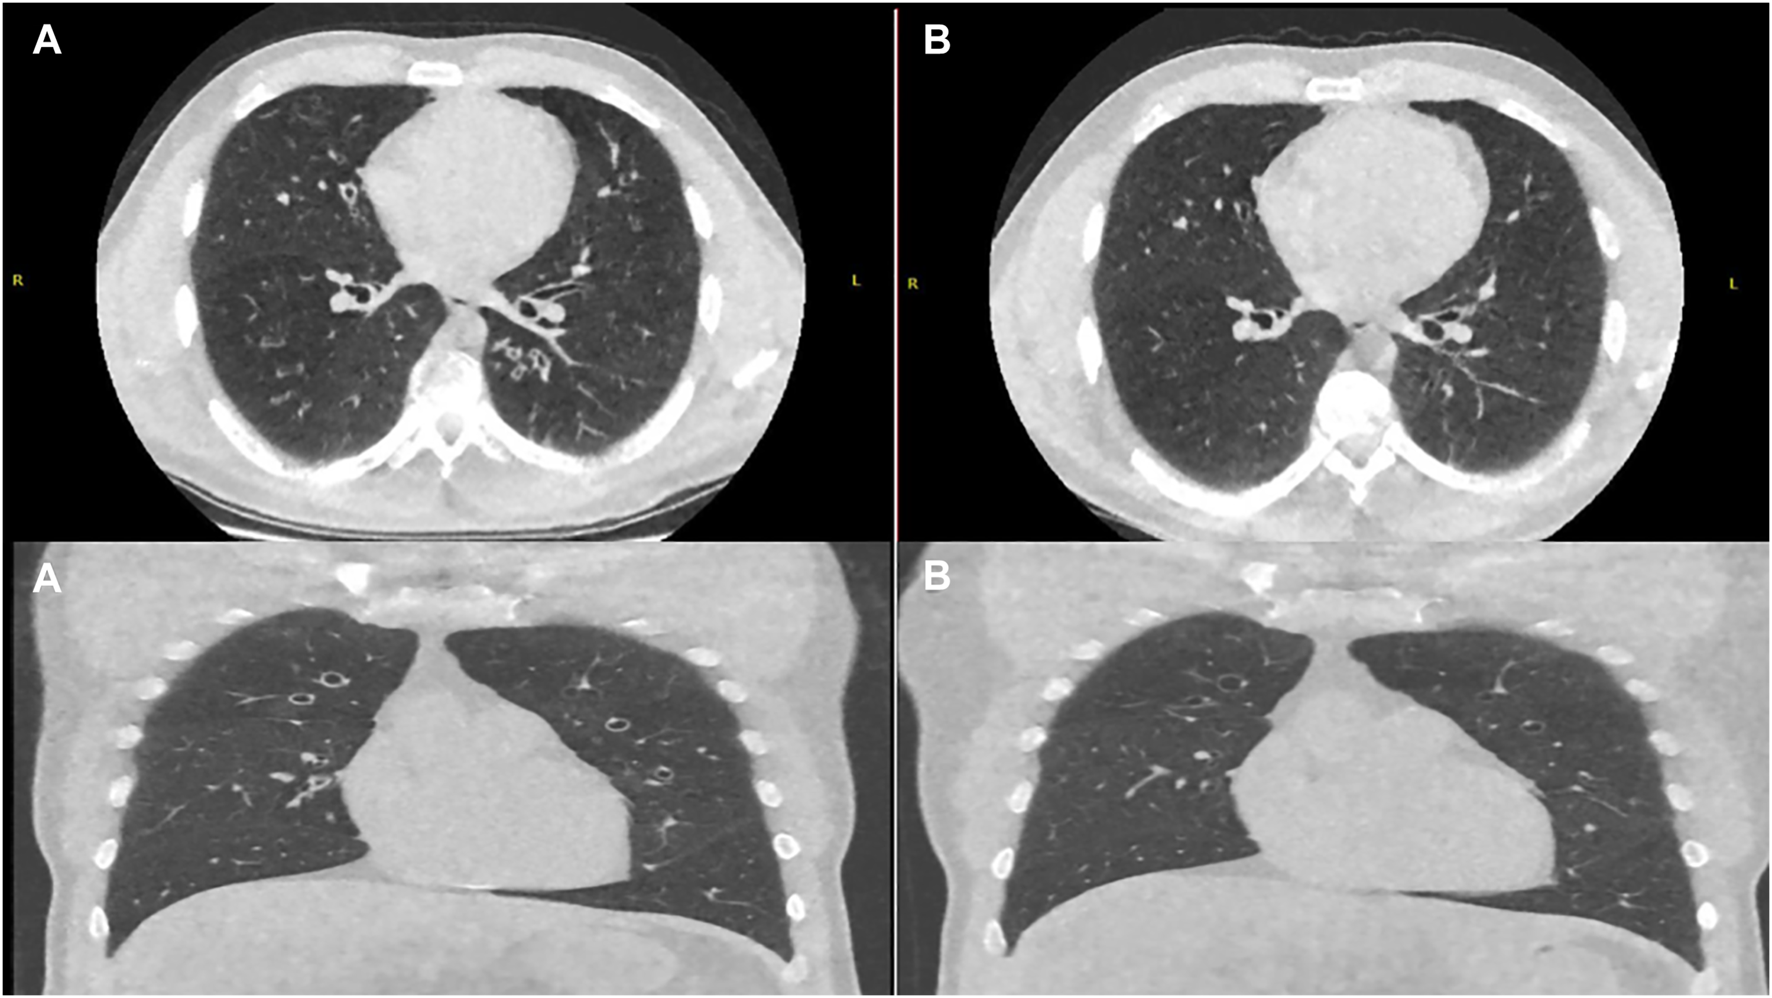

FIGURE 4

Axial and Coronal Ultra-Low Dose CT Thorax pretreatment (A) and post modified dose regimen (B) showing reduction in the degree of bronchial wall thickening and mucoid impaction.